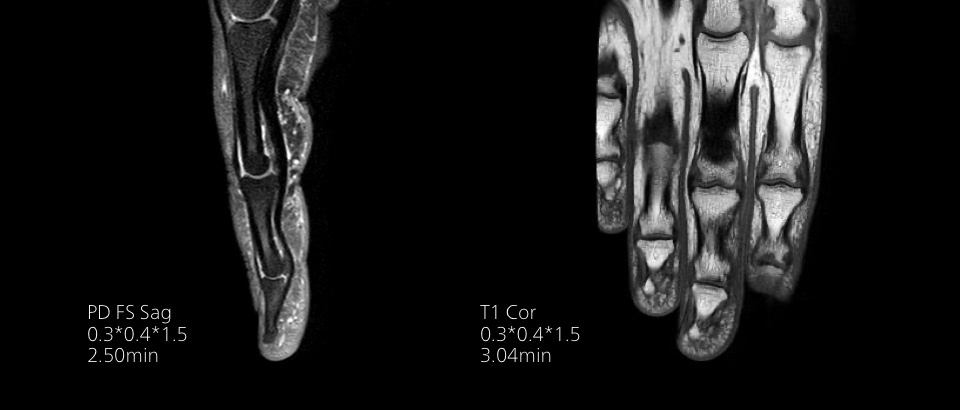

Imagenología de diagnóstico de alta calidad

Nuestras bobinas Breeze ultraligeras aportan versatilidad y crean imágenes uniformes de alta calidad para cualquier anatomía.

Imágenes de calidad para diagnósticos de calidad

Nuestras bobinas Breeze ultraligeras aportan una versatilidad extraordinaria para obtener imágenes de anatomías complejas y las articulaciones más pequeñas. Además de la excepcional calidad de imagen, ofrece un gran campo de visión de 55 cm y un SNR premium.